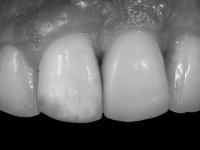

After 12 weeks the restorative procedure was initiated with a first impression to prepare a screw retained lab restoration. A temporary abutment for bone level implant was used to create a proper emergence profile. Two months after the placement, the peri-implant soft-tissue configuration was considered adequate to allow the final impression. In order to satisfy the high esthetic demands of the patient, the fixed rehabilitation was made with zirconium oxide abutment and a press lithium disilicate glass-ceramic restoration.

At the end of the treatment, a stable dental occlusion was accomplished. The midlines of both arches were aligned with facial midline and a correct overjet, overbite and bilateral Class I canine relationships were obtained. The rehabilitation of the left maxillary central incisor loss was accomplished with an implant and a ceramic crown placed after the proper alignment of the adjacent incisor teeth, rendering a complete anterior dentition and a nice smile.